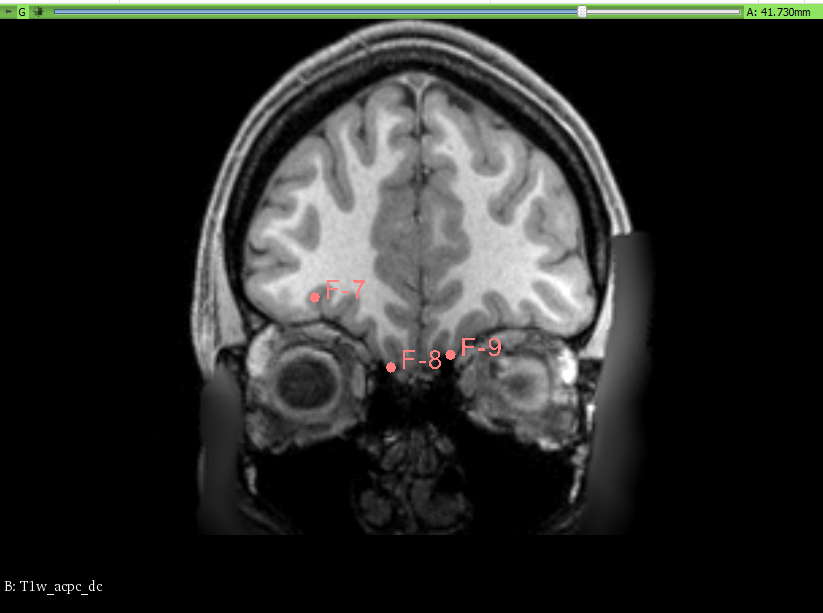

We have taken, for the OFC, the traditional approach, following the olfatory surcus. Fiducial points were placed on the slices for guidance.

The Slicer module used was the Segment Editor. Once the fiducial points were placed, marking the boundaries, slice by slice, the draw/paint and erase tools (with an 1 to 3% diameter) were used to manually trace and fill the corresponding areas for each segment. No other segmentation tools were used, as the work was done in an entirely manual way.

| Placement of the fiducial boundaries |